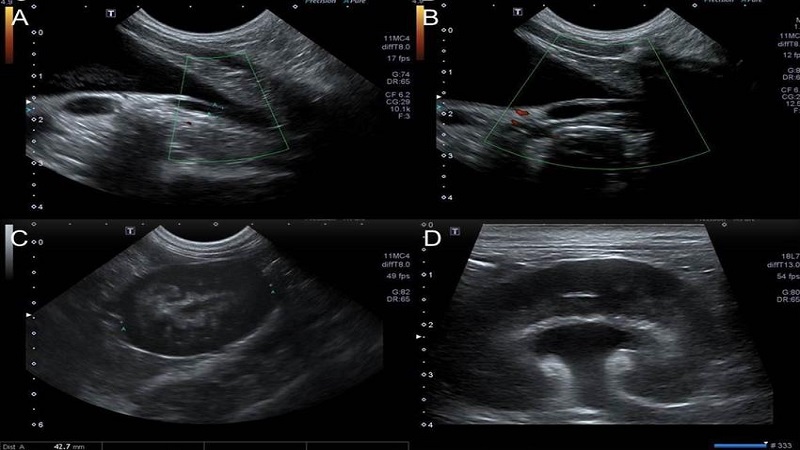

Để chẩn đoán bệnh, bác sĩ sẽ áp dụng lần lượt các phương pháp sau: